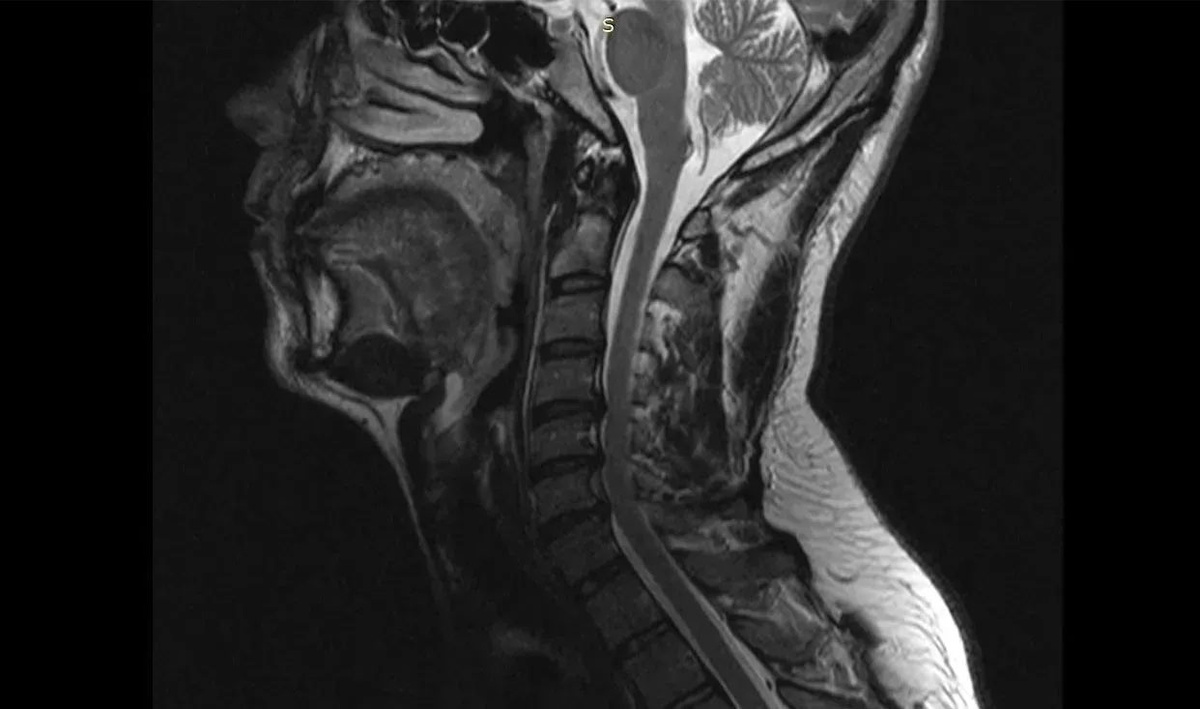

Шейный отдел позвоночника пациента до операции. Изображение: министерство здравоохранения Воронежской области

В стационаре ему диагностировали диско-остеофитный стеноз позвоночного канала на уровне нескольких шейных позвонков. Это означает, что произошло сужение канала, а расположенные в нем структуры оказались сдавленными.